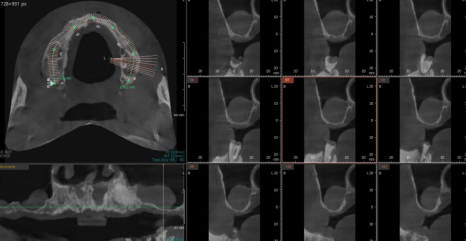

디지털 임플란트 기술을 활용

미리 모형도 제작하여

당일 한번에 위아래 전악 임플란트를 식립하기로 하였습니다.

미리 네비게이션 기술을 활용하여

수술 식립 각도, 사이즈를 분석했습니다.

잇몸 절개를 꼭 필요한 부위만 진행

출혈, 붓기를 감소시킬 수 있었고

실제 수술 시간은 1시간이 조금 넘어 끝났습니다.